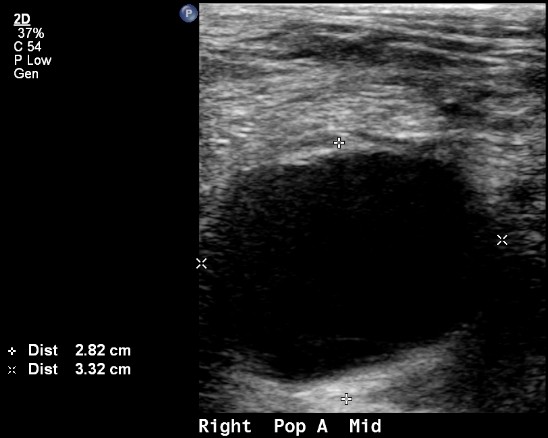

Popliteal artery aneurysm

A dilatation of the popliteal artery by more than 50% normal results in a popliteal artery aneurysm. A normal popliteal artery measures 0.7-1 cm, so an aneurysm is considered when the artery measures more than 1.5 cm in diameter. A popliteal artery aneurysm may remain asymptomatic or result in limb threatening ischemia.

Popliteal artery aneurysm ultrasound

Most popliteal aneurysms, however, are diagnosed with imaging. Arterial duplex ultrasound is a very convenient way to look for a popliteal aneurysm. It is safe, painless and accurate. Ultrasound also offers information about other structures such as a Baker’s cyst or masses. Ultrasound also allows looking for other aneurysms, such as in the contralateral popliteal artery, an abdominal aortic aneurysm or femoral and iliac aneurysms. All of these should be looked for in patients who are diagnosed with a popliteal aneurysm for the first time.